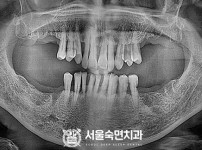

임플란트-전후사진2